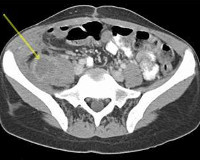

• Томографические методы. На МРТ и КТ выявляются утолщение и нарушение структуры мышцы. При сформировавшемся абсцессе просматривается полость, при прорыве гноя за пределы мышечной фасции определяются затеки.